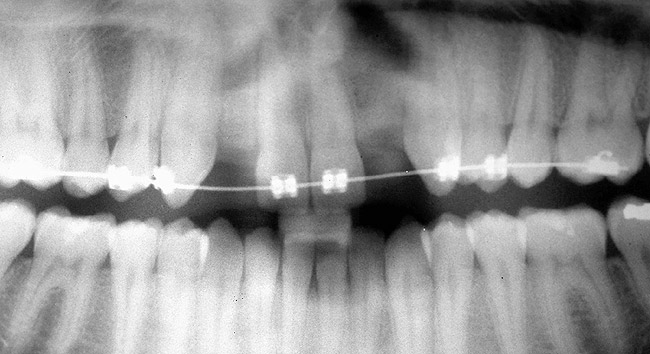

Periapical radiographs were taken to help determine the mesial-distal inclinations of the adjacent tooth roots (Figure 1). The radiographs revealed a serious issue, convergent roots for the right canine and right central, which eliminated that area as a potential implant-receptor site. The space between the left central and canine teeth was minimal, although the roots were relatively parallel. Clinical examination (manual palpation of the root eminences superiorly to the vestibule on the right side) confirmed the root convergence (Figure 2). The flat, wide zone of the keratinized tissue and lack of interdental papilla was evident for the missing right lateral incisor. There was a marked difference in clinical appearance for the left lateral, which could impact the eventual plan of treatment (Figure 3). Other significant clinical findings included bilateral facial bone concavities, which existed as a result of the congenitally missing tooth roots. As a diagnostic cue to the underlying bone topography, it is important to follow the demarcation between attached and unattached gingival tissue, and note the crestal width of the available keratinized tissue (Figure 4).

After several additional months, a panoramic radiograph was provided by the orthodontist to evaluate the distance between the clinical crowns and tooth roots (Figure 5). The lack of sharpness, definition, and radiographic artifacts made it impossible to determine whether implants could be successfully placed based on the 2D panoramic image. This diagnostic predicament was discussed with the patient and his parents, and it was suggested that a CT scan would be necessary to accurately assess the bone topography and spatial orientation of the adjacent roots. The parents agreed, and the patient was given a prescription for a CT scan study at a local radiology center.

Figure 5  DIAGNOSTIC INFORMATION After orthodontic therapy, the radiograph did not provide enough diagnostic information to determine if implants could be placed.

Figure 5